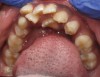

Mouth breathing has also been associated with dental malocclusions in children.2 Zicari and colleagues' analysis of 71, 6- to 12-year-old mouth breathing children revealed a 72.5% incidence of reduced transverse diameter of the maxilla and increased vertical dimension, a 32.5% incidence of cross bite, a 43.7% incidence of skeletal class II malocclusions, and a 90% incidence of atypical swallowing patterns. The results showed a strong correlation between oral breathing and malocclusions, which manifests as both dentoskeletal and functional alterations, leading to a dysfunctional malocclusive pattern (Figure 1 through Figure 3). The study concludes that “this dysfunctional malocclusive pattern makes it clear that the association between oral breathing and dental malocclusions represents a self-perpetuating vicious circle in which it is difficult to establish if the primary alteration is respiratory or maxillofacial. Regardless, the problem needs to be addressed and solved through the close interaction of the pediatrician, otorhinolaryngologist, allergologist, and orthodontist.”

(3.) In children, mouth breathing with low tongue posture can result in narrow maxillary arches, dental crowding, tongue scalloping, and anterior open bites. Images courtesy of Kevin Boyd, DDS, MSc.

Figure 3